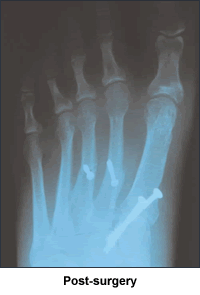

I felt foolish at the appointment, because my feet weren't particularly hurting, I hadn't had an accident and they were just my "normal" feet. Dr. Leavitt was amazed looking at the x-rays at how deformed my feet really were. He had such compassion and empathy and stressed how the operations would be major ones, but that he could really fix my feet from the metatarsal on. Not many doctors could do this. My first doctor definitely did not. When he broke my toe, he was putting a splint on the top of a tree that was crooked at the base (Dr. Leavitt's analogy). Dr. Leavitt said to take my time and think about it because I would be unable to use each foot for 8-10 weeks. A wave of shock and gratitude swept through me as I realized he was talking about giving me totally normal feet. I wanted to get started and shortly thereafter Dr. Leavitt operated on my first foot. Six months later, he operated on my other foot. I have a cast on as I write these words.

Thanks to Dr. Leavitt, I am going to be able to walk side-by-side with my family and dance and shop and not lie awake in agony at night. Dr. Leavitt has increased the quality of my life immeasurably. I cannot recommend Dr. Leavitt highly enough.